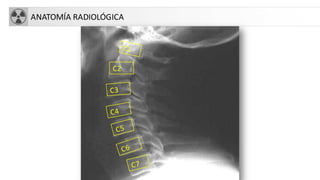

ANATOMÍA RADIOLÓGICA

Evaluación columna cervical:Alineación

• Anterior de los cuerpos

vertebrales

• Posterior de los cuerpos

• Posterior del canal

medular

• Puntas de los procesos

espinosos

BUSCAR DESALINEACIONES.EVALUAR LAS 4 LÍNEAS PARALELAS

1. Línea vertebral anterior

2. Línea vertebral posterior

3. L. espinolaminar. Margen post

del canal medular

4. Puntos que unen las espinosas

COLUMNA CERVICAL

• Una serie adecuada incluye:

• Proyección lateral de columnacervical con

rayo horizontal

• Deben visualizarse:

• Base de cráneo

• 7 vértebras cervicales.Valorar tracción de

hombros.

• 1ª vértebra torácica si es posible

• AP

• Proyección de odontoidescon boca abierta

• Sin movilizar al paciente